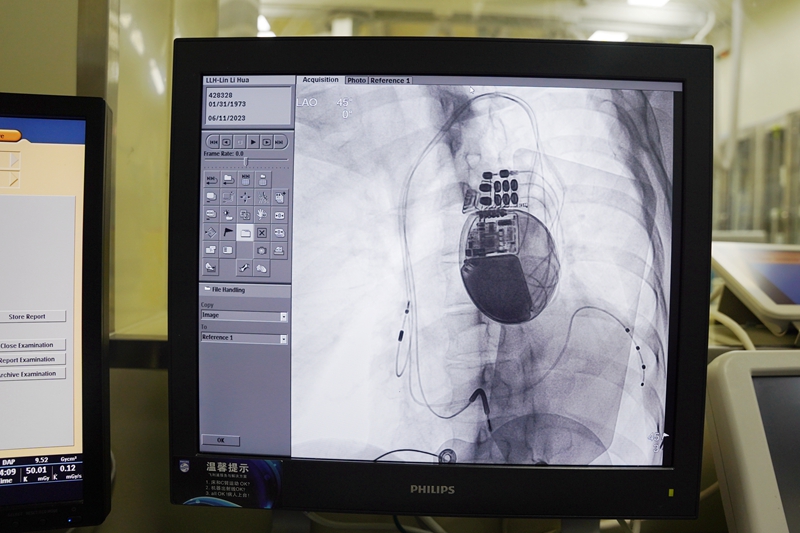

6月11日下午,在浙江省人民医院周颖主任医师的指导下,心内科主任阮宏标、主治医师林权为华女士植入了三腔心脏起搏器,通过血管鞘将三条主动电极植入左心室、右心房、右心室,随后操作起搏器对其心脏实施了心脏再同步化治疗。

术后第一天,华女士的QRS波间期缩短至133ms,接近正常水平,胸闷、气促等症状改善。

林权介绍,三腔起搏器(CRT-D)主要用于治疗对QRS波增宽、左右心室收缩不同步的心衰患者。

它既有心脏同步起搏功能,又有除颤功能。病人心跳很慢时,帮助心脏起搏跳动,协调左右心室同步收缩,改善心脏功能;病人出现室速、室颤时,会自动识别及时进行电除颤,防止病人发生猝死。